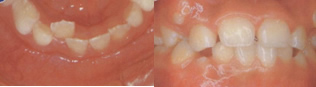

開咬

上の写真は口呼吸をしている子供と鼻呼吸をしている子供の写真です。左の子供の口元は緊張しており、無理やり口を閉じている様子がわかりますか。正常な鼻呼吸ができないために常に口呼吸をおこない、そのために歯が前にでてきて、いざ口を閉じようとしても閉じられなくなっているのです。お口の周りの筋肉がうまく発達できずに「口がポカン」と開けている子供さんを見たことはありませんか??

「上の歯がでている」=『上顎前突』・ 「上下の前歯がきちんと噛んでいない」=『開咬』があります。

D.開咬

口を閉じても前歯や横の歯が上下で噛み合わない。物が噛み切れない場合もある。発音が不明瞭になる。(「さしすせそ」などの摩擦音が特にしにくく英語の場合などはとくに大きなハンディとなります。)

前歯の開きが6ミリメートル以上の場合は要注意です。

・口腔の検査に当たっては、お口の中だけでなく、顎、顔面の全体、口唇、口角、舌、舌小帯、口蓋、その他口腔粘膜等の異常についても注意しております。健診をさせていただき、子供たちの歯並びの悪い・悪くなる可能性の多いお子様が年々多くなっているのではないかと思います。私が最近増えていると心配しているのは下の写真のように咬み合わせが偏位(いがんでいる)しているお子様です。